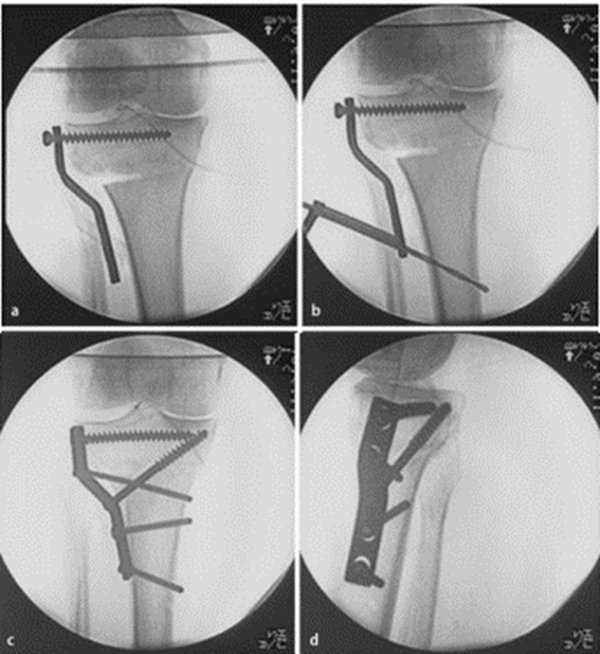

胫骨高位截骨结合外固定支架治疗

Cengiz Sen等治疗53例,取得良好疗效。相对于采用内固定术治疗,外固定支架可避免矫正度数丢失,胫骨近端骨缺失等,可以延缓关节炎进展。

开放楔形截骨,采用不同固定方法,结果显示:外侧合页破坏时,钢板螺钉固定组比骑缝钉固定组、外固定支架组,能够提供更好的稳定性。

病例2:男性,19岁,因发现右膝关节内翻、过伸畸形伴跛行5年(左侧膝关节也有类似畸形,暂时无症状)。于2006年7月就诊,其母亲也有类似病史。查体:右膝关节内翻畸形约15度,应力下过伸约20度,内翻及外翻时膝关节均有松动感,Lanchman试验(+)。无负重下X片示:右膝关节内翻畸形约15度,胫骨平台无后倾,倒呈前倾13º。膝关节MR示:右膝内侧股骨及胫骨软骨面已有缺损并囊性变。诊断:先天性膝关节内翻畸形(Blount病)。

术前X线可见右膝关节内翻畸形约15°,胫骨平台前倾畸形13°

术后6月X片示右膝内翻、前倾畸形已矫正,胫骨截骨处愈合,腓骨未愈合,但无症状。